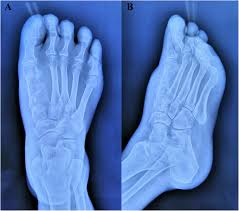

Pain from bone tumors can originate from within the bone. Symptoms of a bone tumor may include: As you learn more about bone cancer, you may become more confident in making treatment decisions. The world health organization has identified 82 different benign and malignant foot lesions. Basal cell cancers may appear as pearly white bumps or patches that may ooze or crust and look like an open sore. Although rare, bone tumors can occur in the foot and ankle. Occasionally a mass or swelling in the area. Grade 1 (g1) means the cancer looks much like normal bone tissue. Sometimes, people with bone sarcoma do not have any of these changes. Each of these types of cancer has their own set of symptoms and treatment, but the main symptom in all of these is a swelling or ulcer on the foot or toe. Bone cancer can weaken the bone it's in, but most of the time the bones do not fracture (break). A benign bone tumor of the foot will manifest as a lump, with or without pain, whereas bone cancer is most often accompanied by pain at the location of the tumor. Whether primary or metastatic, cancer in the bones may present with symptoms such as increasing pain, swelling and/or a more sudden intense pain from a pathologic fracture —a fracture that occurs in a bone that has been weakened by the presence of tumor.

Lumps, swellings, fractures, joint tenderness and pain are some common symptoms of bone cancer in ankle and foot. Squamous cell carcinoma is the most common form of cancer on the skin of the feet. Early on, the pain may only occur at night, or when you are active. When a bone tumor grows, it presses on healthy bone tissue and can destroy it, which causes the following symptoms: The bone may look ragged, or it may appear to have a hole in it.